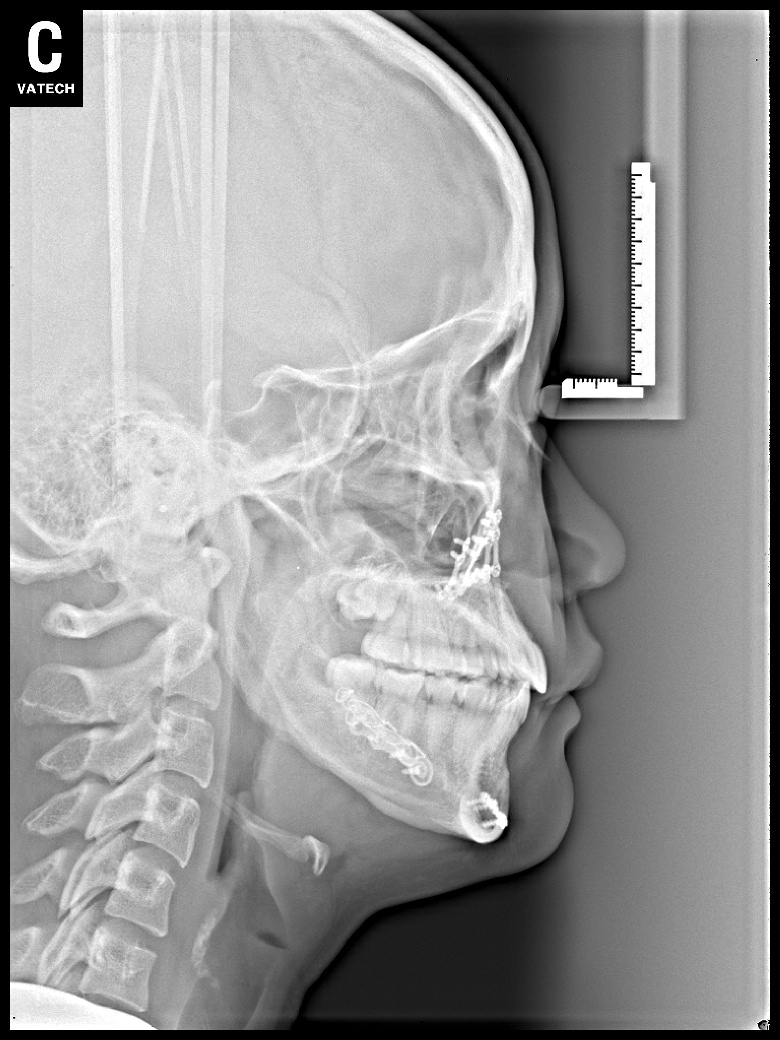

치료 후 사진입니다.